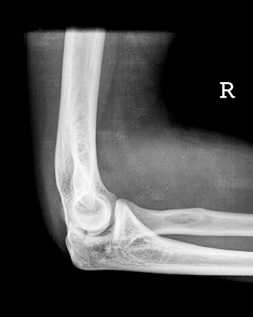

Проекции рентгена локтевого сустава

- Как правило, при проведении рентгена локтевого сустава используются снимки в двух проекциях: переднезадняя и боковая.

- В зависимости от предполагаемой патологии или травмы локтя, рентгенолог может изменить угол среза снимка или положение локтя.

- Рентгенолог также может провести снимки локтевого сустава в согнутом или разогнутом состоянии, в зависимости от целей диагностики.